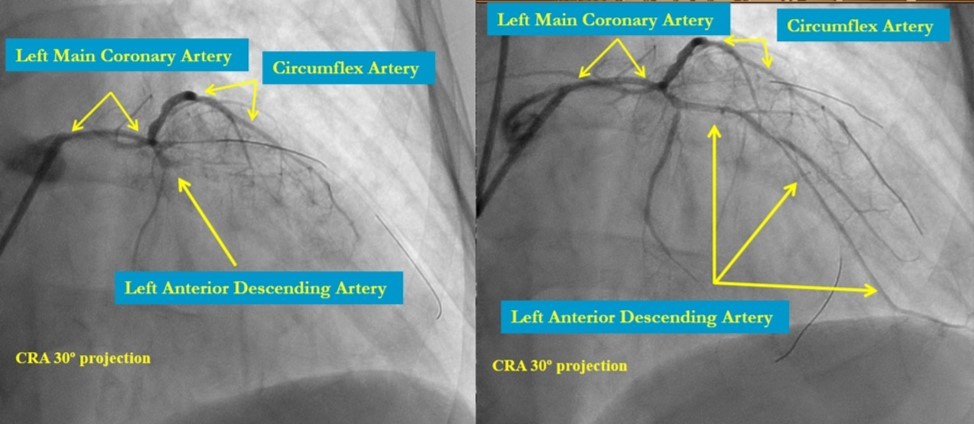

In the first stage, occluded left main and circumflex arteries were recanalized utilizing the support-balloon technique, and CTO wires (Miracle 3™ wire, Abbott Vascular; Runthrough® NS Intermediate wire, Terumo) and balloon pre dilatation was done (Figure 3). In the second stage, the occluded LAD artery was successfully recanalized by utilizing the support-balloon technique, and CTO wires (Figure 3) (due to severe calcinosis the second stage lasted 40 min). In the third stage, LAD artery, CX artery, as well as LMCA and its bifurcation, were stented with 3 drug-eluting stents (Resolute Integrity Zotarolimus DES, Medtronic), the "Culotte Stenting " technique was used for bifurcation stenting (Figure 4), followed by "Kissing Balloon" post-dilatation technique, and finally, proximal optimization technique was performed in the LMCA. The final angiographic image is good, the intervention ended without complications (Figure 5).

Figure 3.LMCA, CX, LAD after recanalization and predilatation